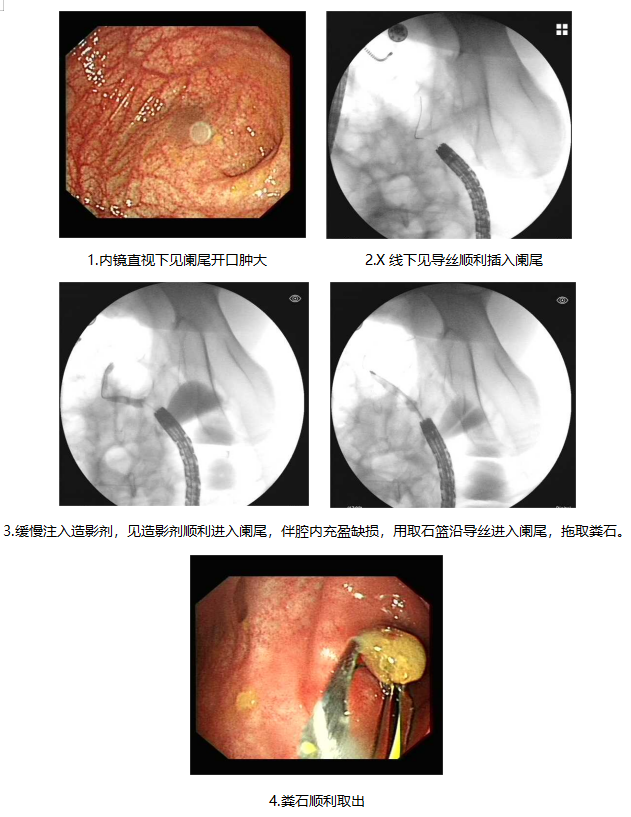

消化内科一病区李俊主任了解病情后,考虑到患者年龄较小,组织团队制定了周密的手术计划,详细向患者家属介绍手术的操作过程、微创性及优缺点。经患者家属同意后,在消化内镜室行内镜逆行性阑尾炎治疗术,术中将阑尾腔内大量粪石及脓性分泌物冲出,术后查体患儿腹痛明显缓解,择期出院。

内镜逆行性阑尾炎治疗(endoscopic retrograde appendicitis therapy, ERAT)与常规外科阑尾切除术有所不同,其理念围绕着超级微创术展开,是从人体自然腔道进入,通过内镜插入回盲部,进行插管、冲洗减压、粪石取出、扩张狭窄阑尾腔、放置阑尾支架以及引流脓液等多种治疗手段来治疗阑尾炎,其优势体现在疼痛迅速缓解、保留阑尾完整性和功能、术后并发症少、术后患者恢复迅速、手术费用较低等方面。